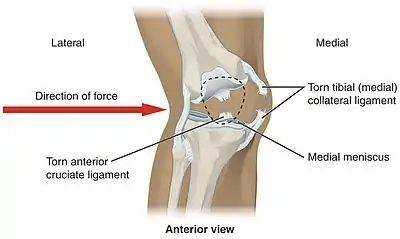

Common injuries due to physical activity

In sports that place great pressure on the knees, especially with twisting forces, it is common to tear one or more ligaments or cartilages. Some of the most common knee injuries are those to the medial side: medial knee injuries.[29]

Anterior cruciate ligament injury

The anterior cruciate ligament is the most commonly injured ligament of the knee. The injury is common during sports. Twisting of the knee is a common cause of over-stretching or tearing the ACL. When the ACL is injured a popping sound may be heard, and the leg may suddenly give out. Besides swelling and pain, walking may be painful and the knee will feel unstable. Minor tears of the anterior cruciate ligament may heal over time, but a torn ACL requires surgery. After surgery, recovery is prolonged and low impact exercises are recommended to strengthen the joint.[30]

Torn meniscus injury

The menisci act as shock absorbers and separate the two ends of bone in the knee joint. There are two menisci in the knee, the medial (inner) and the lateral (outer). When there is torn cartilage, it means that the meniscus has been injured. Meniscus tears occur during sports often when the knee is twisted. Menisci injury may be innocuous and one may be able to walk after a tear, but soon swelling and pain set in. Sometimes the knee will lock while bending. Pain often occurs when one squats. Small meniscus tears are treated conservatively but most large tears require surgery.[31]